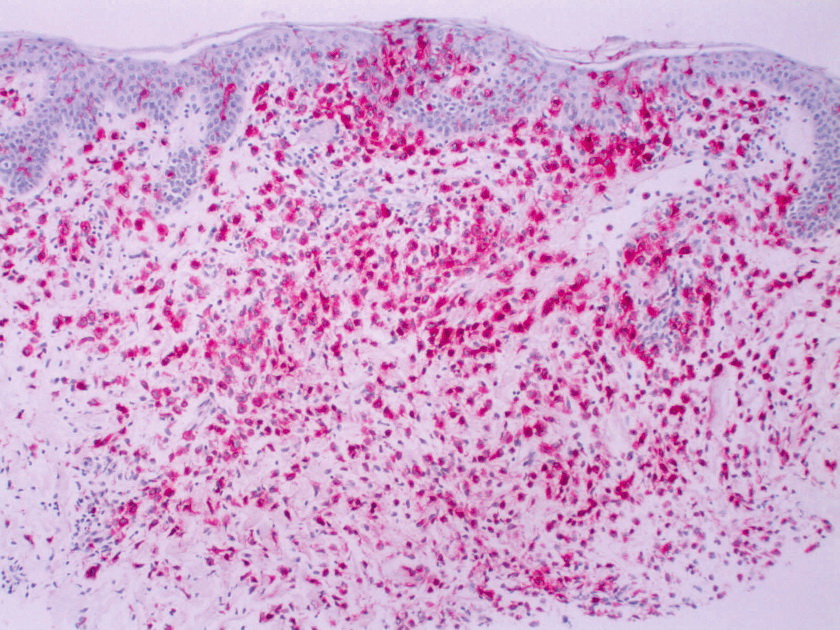

Histiocytosis X =x كثرة المنسجات